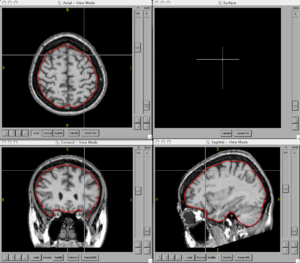

BRAINSCut is a software package for segmentation of structures using artificial neural networks. Currently this tool supports the segmentation of the following structures: brain, caudate, putamen, thalamus, hippocampus, anterior cerebellum, interior posterior cerebellum, superior posterior cerebellum, corpus medullary. Future regions will include the globus pallidus, amygdala, and nucleus accumbens. The command line uses the Slicer3 execution model framework.

Figures

- BRAINSCut